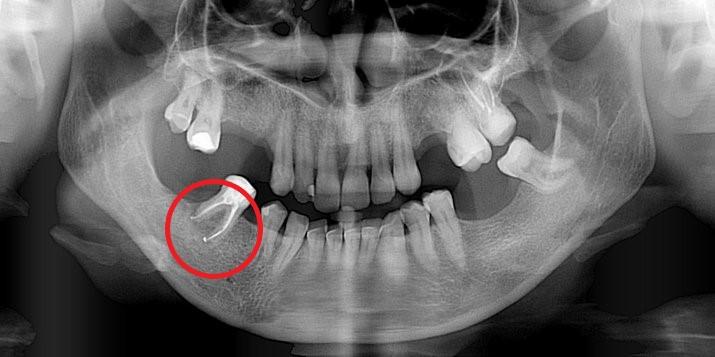

Leczenie kanałowe jest leczeniem skutecznym. Prawidłowe leczenie kanałowe sprawia, że ząb przestaje być ogniskiem zakażenia, a tkanki wokół goją się. Wyleczenie zęba powoduje, że przyczyna choroby tkanek około zębowych [na RTG widzimy jedynie chorobę kości] zostaje usunięta. Eliminacja przyczyny choroby umożliwia gojenie się zmian chorobowych.

Na poniższych zdjęciach RTG – WIDAĆ GOJENIE ZMIAN ZAPALNYCH KOŚCI.

Nie jest prawdą, że leczenie kanałowe w każdym przypadku jest szkodliwe. Ogniskami zakażenia są zęby martwe, nieprzeleczone kanałowo, zęby z nieprawidłowym leczeniem kanałowym i to właśnie one są zagrożeniem i powinny być eliminowane.